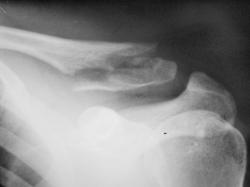

Травма. Перелом ключицы.

значит была неправа - не показалась З-образная линия перелома, хотя теоретически, если была киста, то она при переломе могла самоизлечиться

Если при переломе в области кисты, жидкость изливается, давление внутри кисты падает, кость перестает разрушаться и может репарировать, то при опухоли, а остеобластокластома это именно опухоль (хотя иногда может сочетаться с вторичной аневризмальной кистой), перелом только способствует ее росту, т.к. опухоль "прорывается" в мягкие ткани, где по принципу наименьшего сопротивления ей расти проще, чем в кости.

Единственный вариант, который можно предположить в оправдание таких высказываний следущий: морфологи в кисте иногда видят клетки, подобные гигантским клеткам вОБК, поэтому, если при трепанбиопсии кисты их нашли, могли поставить диагноз "гигантоклеточная опухоль", пациент возможно отказался от операции, а киста могла репарировать... Отсюда ложный вывод о самоизлечении при переломе гигантоклеточной опухоли, которая на самом деле была кистой...